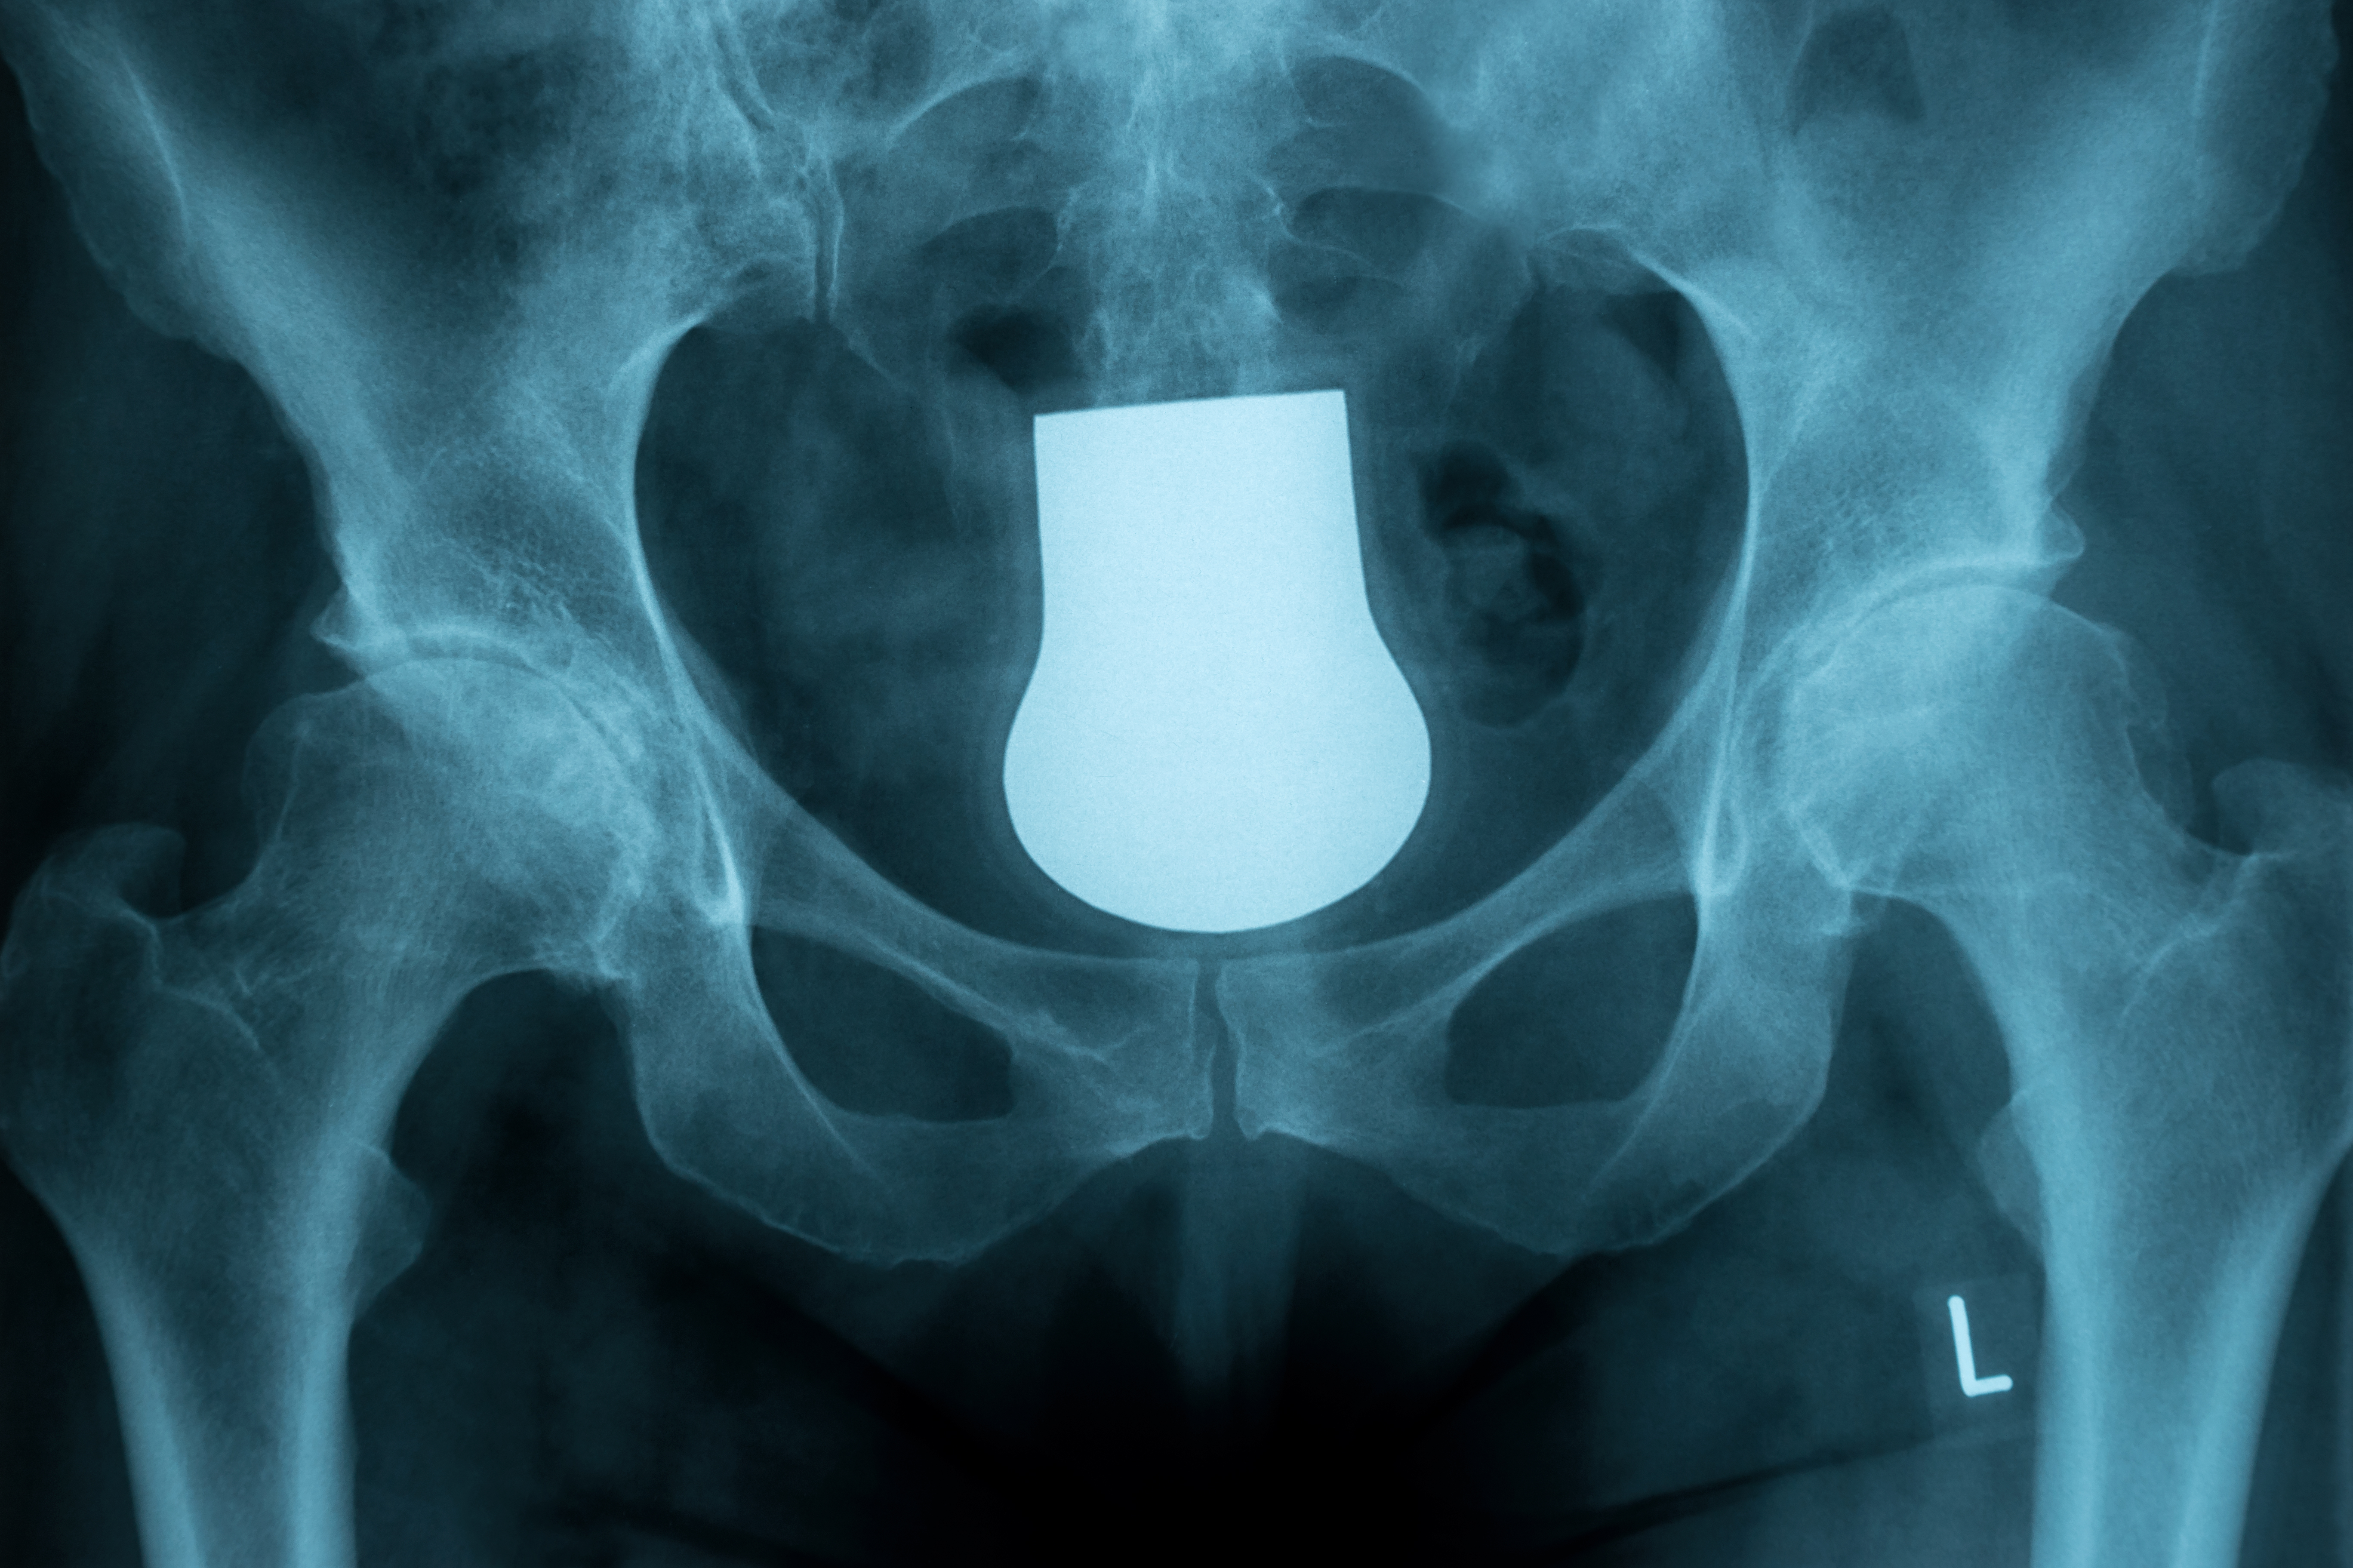

THA的假体安装及软组织平衡,手术要点大汇总!